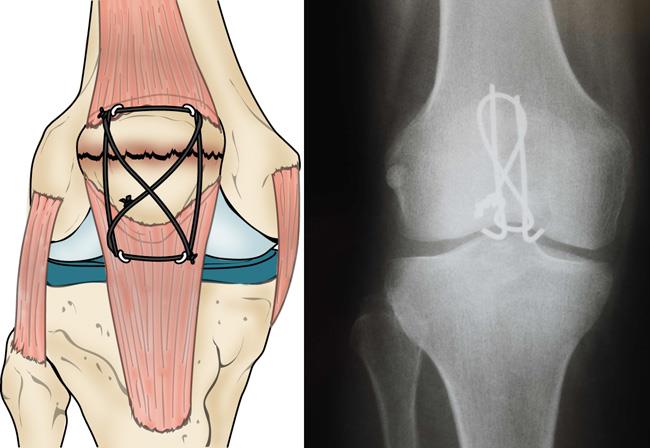

Patellar Fractures (Broken Kneecap

Patellar Fractures (Broken Kneecap

Patella Fracture | Reno Orthopedic Center direct fall on knee cap